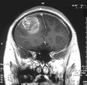

Bu belirtiler malign tümörlerin varlığını gösterebileceği gibi, başka sağlık sorunlarının belirtisi de olabilir. Bu nedenle, belirtilerin ortaya çıkması durumunda bir sağlık uzmanına başvurulması önemlidir. Malign Tümörlerin Tanı YöntemleriMalign tümörlerin tanısı, çeşitli yöntemler kullanılarak konulmaktadır. Bu yöntemler arasında:

Bu tanı yöntemleri, malign tümörlerin varlığını belirlemek ve tümörün türünü, evresini değerlendirmek amacıyla kullanılmaktadır. Erken tanı, tedavi sürecinde büyük bir öneme sahiptir. Malign Tümörlerin Tedavi SeçenekleriMalign tümörlerin tedavisi, tümörün türüne, evresine ve hastanın genel sağlık durumuna bağlı olarak değişiklik göstermektedir. Başlıca tedavi yöntemleri şunlardır: